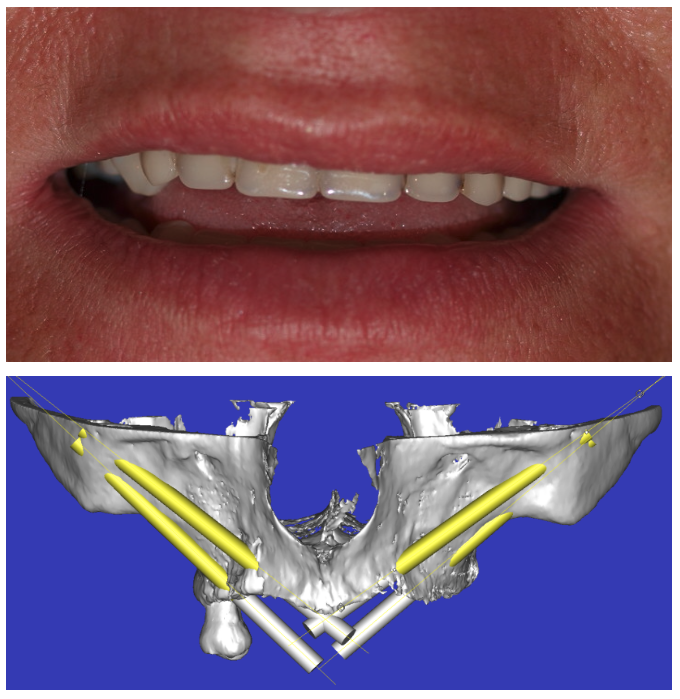

Implantes zigomáticos

Paciente con atrofia maxilar total por MAXILECTOMÍA izquierda (para tratar un Carcinoma epidermoide)resuelta con la colocación de 4 implantes ZIGOMATICOS. La rehabilitación definitiva ha sido en metal cerámica.

Imagen de la planificación digital del caso y foto final de la paciente con la prótesis metal-cerámica.